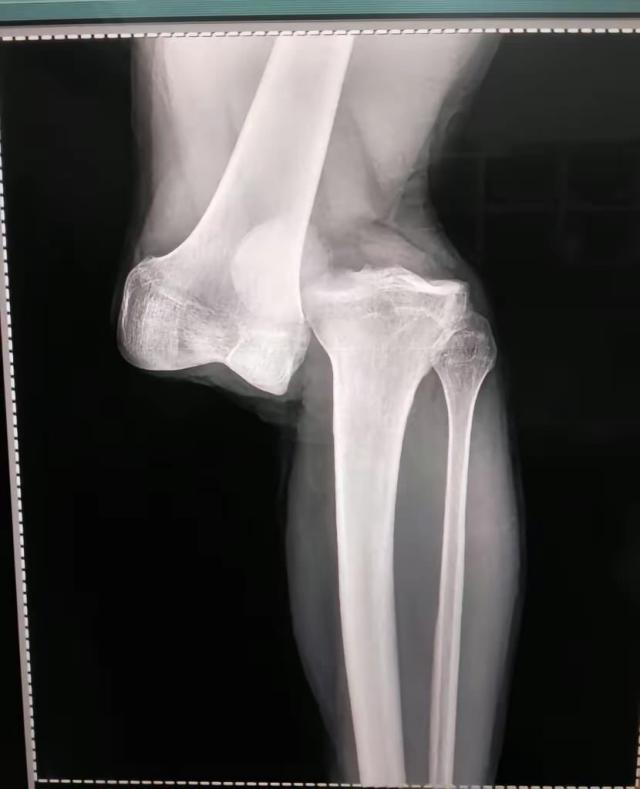

下面是卢西亚诺·桑切斯受伤瞬间照片、在医院病床上拍的腿部照片以及X光检查结果,画面比较强烈,请谨慎考虑是否观看:

X光片

8月2日,做过检查,住院观察一夜之后,卢西亚诺·桑切斯坐着轮椅出了院。他的左膝脱了臼,大腿骨和腓骨分开了,三周之内做手术,可能一次手术还不行,得做多次手术,至少需要休息10个月,甚至有可能是1年。

8月2日接受阿根廷一电台采访,阿根廷青年人俱乐部队医亚历杭德罗·隆科罗尼说:“做了23年医生,我从没见过这么严重的伤病。(阿根廷队队医比利尼)干了40年医生,他对我说他也没见过一样的伤病。是膝盖完全脱臼。大腿骨和腓骨基本上分离了。前后十字韧带都撕裂了,我们还得看半月板情况怎样。”